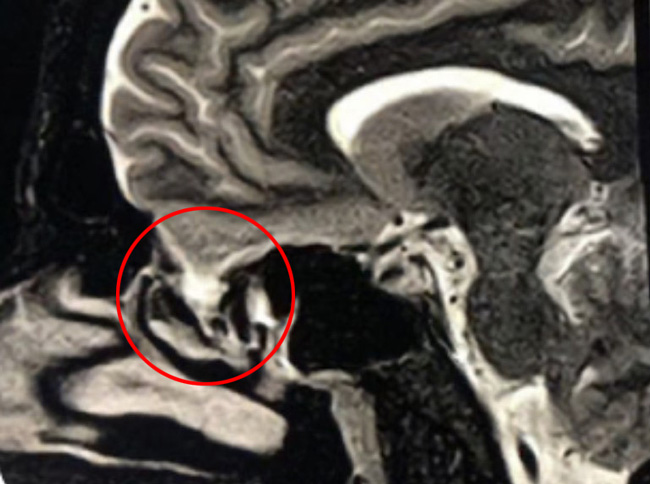

This is a 39 year old physician with a long history of sinus issues, who more recently had noted an increased drainage of clear fluid from his nose. Testing of the fluid for Beta-2-transferrin demonstrated that it was consistent with cerebrospinal fluid (csf). MRI and CT scan demonstrated an encephalocele in the frontal most part of the anterior skull base, on the left, just off midline (Figures 1a,1b,1c). For the last 3 weeks, he has also been having headaches and neck pain.

Figure 1c – Sagittal T2 MRI